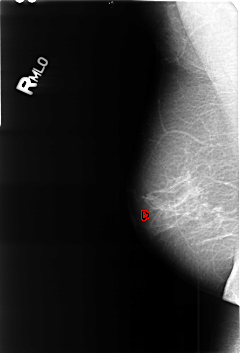

B_3447_1.RIGHT_MLO

RIGHT_MLO LINES 4584 PIXELS_PER_LINE 3120 BITS_PER_PIXEL 12 RESOLUTION 50 OVERLAY

FILE: B_3447_1.RIGHT_MLO.OVERLAY

TOTAL_ABNORMALITIES 1

ABNORMALITY 1

LESION_TYPE CALCIFICATION TYPE SKIN-COARSE-ROUND_AND_REGULAR DISTRIBUTION N/A

ASSESSMENT 2

SUBTLETY 3

PATHOLOGY BENIGN_WITHOUT_CALLBACK

TOTAL_OUTLINES 1

BOUNDARY